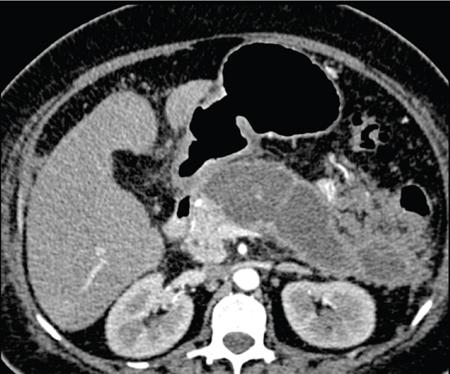

Anirudh Kohli Acute pancreatitis is one of the most dreaded diseases to afflict mankind, in view of its high morbidity and mortality. The single most important factor in reducing the morbidity and mortality of this condition over the last many years has been the role of computed tomography (CT). The incidence of acute pancreatitis is rising especially due to an increasing incidence of gallstones, obesity, as well as an ageing population. Pancreatitis occurs due to a chain of events triggered by a temporary/permanent pancreatic duct obstruction. This leads to activation and release of pancreatic enzymes into pancreatic interstitium and peripancreatic tissues leading to severe auto digestion and necrosis of pancreas and adjacent tissues. Systemically there is release of inflammatory mediators known as cytokines. Tumour necrosis factor is a cytokine which is toxic to acinar cells. These cytokines activate and intensify the inflammatory cascade that may ultimately culminate in multiorgan failure. Clinically severe acute pancreatitis is characterized by two phases, an early phase and a late phase. The early phase is dominated by the systemic effects of release of inflammatory mediators such as cytokines – termed as systemic inflammatory response syndrome (SIRS). Usually there is associated variable multiorgan dysfunction/failure. This phase lasts for a week. When the multiorgan failure lasts 2 days it is termed as mild, multiorgan failure lasting more than 48 hours is considered severe. There is no correlation between the clinical severity of pancreatitis and morphological changes in this early stage. In view of this CT scan is not of much utility during this phase, unless complications are suspected. The later phase is dominated by effects of local complications due to pancreatic/peripancreatic necrosis. Mortality follows this biphasic pattern in early weeks from the systemic effects of multiorgan failure and in later weeks due to local effects, for example infection of necrotic pancreatic/peripancreatic tissues superimposed by organ failure. The Clinical diagnosis of acute pancreatitis requires two of the following three features: If the first two findings are present without any significant SIRS then CT is not required. Acute pancreatitis is a complex disease with a wide variation in the presentation and outcome, ranging from asymptomatic with only biochemical alterations to a fatal outcome. In fact acute pancreatitis is a dynamic disease with continuously evolving appearances on imaging. There are two distinct forms of acute pancreatitis – interstitial oedematous pancreatitis and acute necrotising pancreatitis. Interstitial oedematous pancreatitis is a condition where there is only mild swelling of the pancreas with loss of normal lobulations and a diffuse decrease in attenuation of the pancreas. There may be heterogeneity of the pancreatic parenchyma due to varying degrees of interstitial oedema. This form of pancreatitis runs a mild course and rarely progresses to acute necrotising pancreatitis with its associated complications. In a third of these cases the pancreas may reveal no abnormality on a CT scan. The inflammatory changes may be restricted to the pancreas or extend into the peripancreatic regions. The inflammation in the peripancreatic regions manifests as acute pancreatic effusions. If there is peripancreatic fat necrosis with an oedematous pancreatic gland it is termed as acute necrotising pancreatitis (Figs. 9.17.1–9.17.2). Acute pancreatic fluid collections are enzyme-rich pancreatic juice collections seen in about 40% of patients with acute pancreatitis. The fluid collections occur due to exudation of pancreatic juices into the interstitium of the pancreas and subsequently leakage into the surrounding tissue spaces. These fluid collections are localized only by the anatomic space in which they collect. As the exudative process continues, the parietal peritoneum overlying the pancreas may be disrupted with the inflammatory fluid entering the lesser sac. From the lesser sac the fluid can enter the peritoneal cavity via the foramen of Winslow or by dissecting the peritoneum along the anterior surface of the lesser sac. Posterior extension of the fluid collection in the anterior pararenal space may occur into a potential space between the laminae of the posterior pararenal fascia. Rarely there may be involvement of the perirenal and posterior pararenal spaces. Other pathways of dissection are along the gastrohepatic, gastrosplenic and gastrocolic ligaments. Fluid may dissect along the root of the mesentery into the transverse mesocolon. Collections may extend around the caecum, ascending colon, descending colon and into the lumbar, pelvic and inguinal regions. Large fluid collections may dissect superiorly into the mediastinum or pericardial space. The quantity of fluid in these effusions is variable and can range from a small amount to large quantities (Fig. 9.17.3). Of these collections, 50% resolve spontaneously; the remainder may evolve after 4–6 weeks into pseudocysts. As the collections age, they tend to get localized and walled off, often developing an enhancing wall. A collection should be termed a pseudocyst only when a definite capsule develops and the collection has been static for at least 4–6 weeks. The risk of complications such as rupture, infection and haemorrhage increases with the age of the collection. Large collections of fluid are usually associated with a lesser degree of pancreatic necrosis as compared to extensive pancreatic necrosis associated with a lesser amount of fluid collection. Acute necrotising pancreatitis is a fulminant form of pancreatitis in which there is necrosis of the pancreas, that is nonviable pancreatic tissue. A contrast-enhanced CT is essential as it is the ideal means to demonstrate necrosis as well as to determine the extent of necrosis. These areas of nonviable pancreatic tissue do not enhance as compared to viable pancreatic tissue, which demonstrate significant enhancement. The extent of pancreatic necrosis has been found to correlate extremely well with the extent of necrosis found at surgery. The size, location and extent of pancreatic necrosis are very variable. These areas may be diffuse or focal, small in size to complete glandular involvement. These necrotic areas have a very important bearing on the course of pancreatitis, as they are liable to undergo secondary infection and form pancreatic sepsis. In addition, the more extensive the pancreatic necrosis the greater is the morbidity and mortality. Patients with no pancreatic necrosis have been found to have a 0% mortality and a 6% complication rate, whereas patients with pancreatic necrosis have a 23% mortality rate and an 82% complication rate. A variety of laboratory tests are available to detect pancreatic necrosis, such as a rise in the serum methemalbumin, quantitative estimation of C-reactive protein and urinary trypsinogen-activated peptide. CECT is still the most accurate modality to detect pancreatic necrosis. Pancreatic necrosis may be seen in the pancreas only, peripancreatic tissues also or only in the peripancreatic region. Isolated peripancreatic necrosis occurs due to disruption of the peripheral ductules with extravasation of activated pancreatic enzymes, may be seen in up to 20% of patients who require operative/interventional management of their necrotising pancreatitis. These patients with only peripancreatic necrosis have a better prognosis. This essentially represents retroperitoneal fatty tissue necrosis appearing as heterogeneous areas of liquid and nonliquid components. Over time necrosis evolves and liquefies as well as the liquid component resorbs. Generally if the liquid component is 2 cm or less it will resorb, while fluid collections 5 cm or more rarely resorb. If pancreatic necrosis is not resorbed it may get walled off or with time or may become infected. Encapsulation occurs between the third and fourth weeks. It is important to differentiate sterile from infected necrosis as sterile necrosis rarely needs surgery, whereas infected necrosis requires long-term antibiotic therapy and/or some kind of imaging/surgical intervention. According to the Atlanta 2012 classification, all areas of pancreatic necrosis are termed as acute necrotic collections. This represents a combination of pancreatic/peripancreatic fat necrosis with peripancreatic effusions. On CT, there is a spectrum of findings – solid, liquid containing debris (these may be nonwalled off/partially walled off). Sonography and MRI have advantages over CT scan in demonstration if the contents are pure liquid such as acute pancreatic effusions or have some nonliquefied components such as acute necrotic collections. Pseudocysts are round or oval encapsulated fluid collections containing only liquefied components. It takes 4 weeks for the granulation tissue to develop. On CT, a pseudocyst appears as a well-defined fluid collection with a thin capsule. The most common location for pseudocysts is the lesser sac, though they may be found anywhere in the mediastinum, abdomen or pelvis as they may dissect along fascial planes, along vessels and through capsules of solid organs. Pseudocysts in the bowel, though reported, are relatively rare, as the bowel wall is a strong barrier to the effect of proteolytic pancreatic enzymes. When the contents of the pseudocyst are heterogeneous or uniformly increased in attenuation, the possibilities of infection or haemorrhage should be considered. Focal areas of increased density within the fluid collection usually indicate haemorrhage. Complicated, enlarging or symptomatic pseudocysts require percutaneous catheter or surgical drainage. Infected pseudocysts are treated by percutaneous drainage. The management of a noninfected pseudocyst is controversial. Surgical treatment is only undertaken when the wall is mature after several weeks. Large pseudocysts greater than 5 cm in size can easily be drained percutaneously using intercostal drainage tube or pigtail catheter or endoscopically via the stomach. The cure rates are reported to be 85% with percutaneous drainage, the drainage period averaging about 20 days (Figs. 9.17.4–9.17.5). Walled off necrosis – as pancreatic/peripancreatic necrosis matures and evolves, an interface develops between necrosis and adjacent fatty tissue and an enhancing thickened wall is seen, resulting in a well-defined fluid collection with necrotic debris and fat necrosis. This is the end stage in the evolution of an acute necrotic collection. It is important to differentiate a pseudocyst from walled off necrosis, as a pseudocyst requires drainage and walled off necrosis requires surgical removal (Figs. 9.17.6–9.17.9). Sepsis is a major complication of pancreatitis and is accompanied by a high incidence of mortality and a prolonged hospital stay. Pancreatic sepsis may occur following secondary infection of pancreatic and/or peripancreatic necrosis, acute pancreatic fluid collections and pseudocysts. The only specific sign to demonstrate sepsis is the presence of gas in a collection. This occurs due to secondary infection by coliform/anaerobic organisms. This sign is unfortunately not common and seen in only one-third of cases. Gas is seen in the fluid collection as very dark well-defined air attenuation bubbles. Occasionally gas may be present due to a gastrointestinal fistula or previous surgery. Fat necrosis is seen in peripancreatic collections. This should not be confused with air bubbles, which are indicative of sepsis. The differentiation is easy to understand by CT, the values of fat ranging between – 20 HU and – 80 HU, and of air being >–300 HU. Also air bubbles have well-defined margins and are homogeneously jet black, whereas fat is nonhomogeneously grey with ill-defined margins. Since the presence of air is seen only in a small percentage of patients with pancreatic sepsis, the only other means to diagnose pancreatic sepsis is by CT-guided aspiration. All sites of fluid collection, parenchymal necrosis and peripancreatic necrosis are subjected to CT-guided aspiration. This is a tedious process and requires a dedicated interventional radiologist as there are often more than 5–6 sites from which it may be necessary to obtain samples. A fresh needle and syringe are used for each site, as it is important to know which site has sepsis and which is sterile. Care is taken not to transgress the large bowel as the colon has a large number of bacteria, and transgressing it could result in colonic bacteria contaminating the CT-guided aspiration sample, with falsepositive results. Further, colonic bacteria may be inoculated into a sterile acute pancreatic fluid collection or necrosis thereby converting a sterile collection into an infected one (Fig. 9.17.10). Complications of the procedure can be pneumothorax if the pleura is transgressed, haemorrhage due to trauma to a vessel, and secondary infection. Pancreatic sepsis is treated by surgical debridement, necrosectomy and drainage through thick tubes. It is crucial from the management point of view to differentiate an abscess from infected necrosis. An abscess may be treated by percutaneous drainage, whereas infected necrosis developing in relatively solid tissue can be treated by surgical debridement alone. Imaging-guided percutaneous drainage is the first step in treating pancreatic sepsis especially patients who are very ill and cannot undergo surgery. Initially pig tail catheters were used but these are notorious to get blocked as the largest bore of a pigtail catheter is 12 F. Pancreatic sepsis contains a large amount of necrotic debris, this blocks the catheters can be cleared by flushing the catheter, but this always raises the possibility of introducing secondary infection. To circumvent this issue large-bore ICD catheters have been introduced. These range from 16 F to 30 F. A safe window is necessary, not transgressing bowel or vasculature. It is quite easy to insert these tubes percutaneously under CT. A bit of initial manipulation and force is required to pierce the abdominal musculature. These large-bore drainage tubes have been very effective unless the infected necrosis is solid with minimal liquefied contents or a safe window for placing an ICD catheter is not available. CT is also invaluable in surgical planning and in the follow-up of postoperative patients to evaluate any fresh collection and also to determine whether the drains are well sited or not (Fig. 9.17.11).